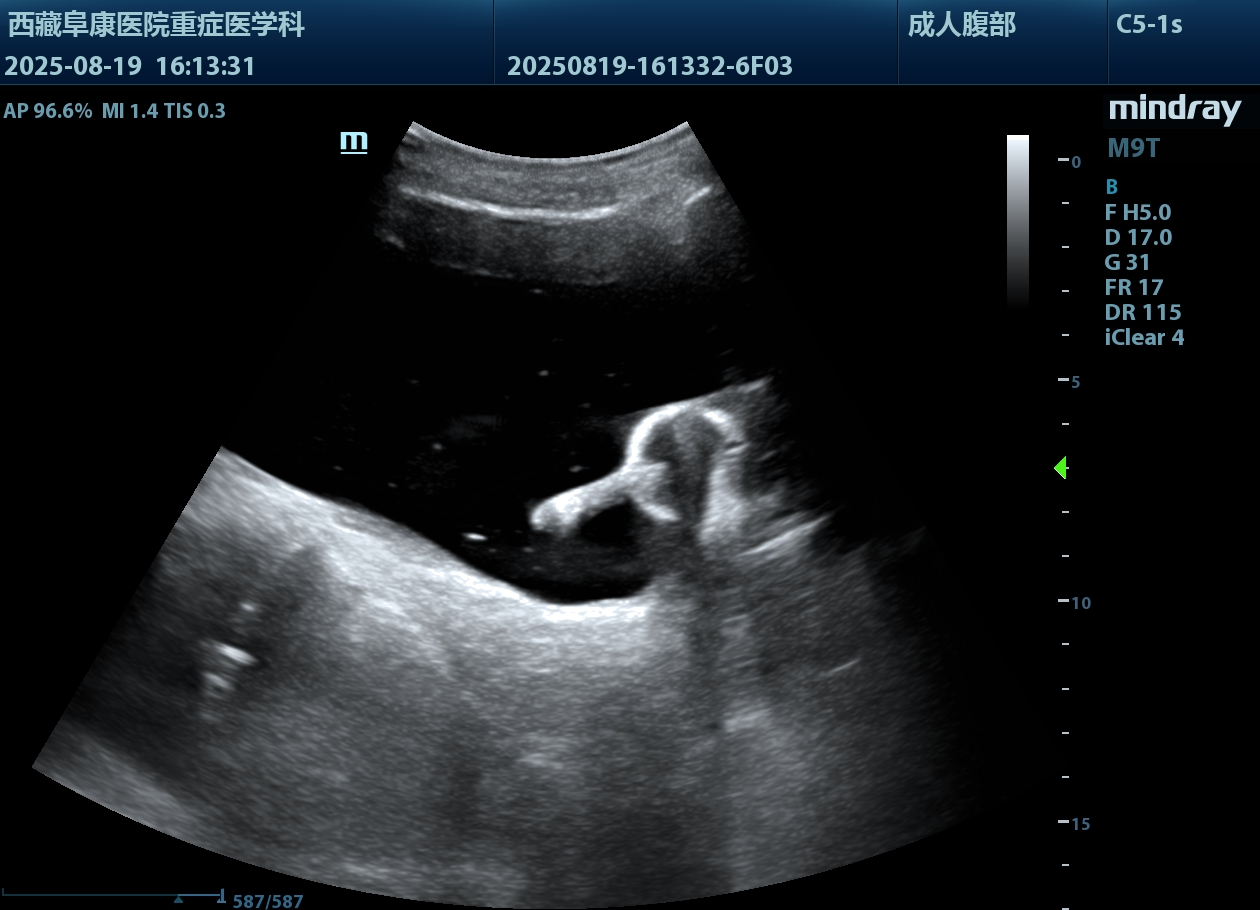

由于情况紧急,医护人员没有半分迟疑,除了导尿所需的物品,考虑到老人年纪大了,必须先确认情况,半点马虎不得,他们特意带上B超机,拎起出诊箱,火速赶往老人家中。

推开门,只见老人蜷缩在藏式床上,身子微微发颤。医护人员放轻脚步,俯身轻声安抚:“大爷,我们先帮您看看情况,不难受的。”先是轻柔查体,感知膨隆小腹下的膀胱充盈度;再用B超机细致探查,医护人员边操作边低声讲解流程。慢慢地老人紧绷的身体放松下来,默许了检查。可是提到导尿时,还是摆着手抗拒。医护人员和家属耐着性子反复劝说,许久后,他终于轻轻点了头。